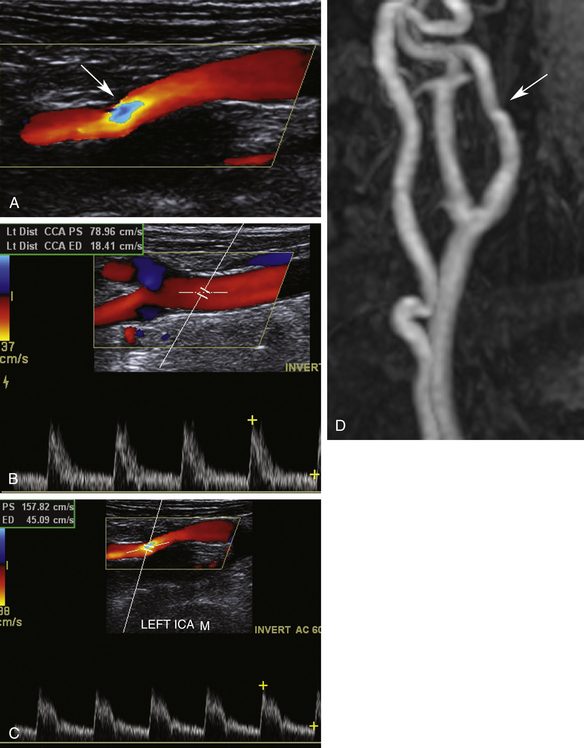

У этого 58-летнего мужчины случился обморок. Посмотрите на результаты, представленные на рисунке 10-15 , и оцените поражение левой ВСА.

РИСУНОК 10-15. Случай 5. А. Цветное допплеровское изображение левой внутренней сонной артерии (ВСА). Б — Цветное и импульсное допплеровское изображение левой общей сонной артерии (ОСА). C, Цветное изображение и импульсные допплеровские сигналы левой ВСА. D, Магнитно-резонансная ангиограмма левой сонной артерии.

Оценка

Цветная допплерография левой ВСА демонстрирует область наложения спектров, соответствующую повышенным скоростям и фокальному стенозу. ПСВ в середине ВСА составляет 158 см/сек. В этой области сосуда не наблюдается фокальной бляшки или значительного сужения просвета. PSV в дистальной ОСА составляет 79 см/сек. Соотношение ICA/CCA составляет 2:1. Измерения скорости и соотношение предполагают стеноз левой ВСА от 50% до 69%. В правой сонной артерии бляшек или повышенной скорости не наблюдается.

В этом случае сбивает с толку повышенная скорость в средней части ВСА без соответствующей бляшки. Это нетипичная локализация атеросклеротического заболевания. Более того, судно поворачивает в месте совмещения, что указывает на извилистость или излом. Магнитно-резонансная томография/магнитно-резонансная ангиография проводилась в рамках обследования обморока.

Диагностика

Излом средней части ВСА, подтвержденный при магнитно-резонансной ангиографии.

Что следует помнить

1. Большинство стенозов ВСА возникает в бифуркационных и проксимальных сегментах ВСА.

2. Стеноз обычно характеризуется сужением просвета и образованием бляшек.

3. Очаговое повышение скорости может возникать в области извилистости или перекручивания сосудов.

4. Рассмотрите возможность корреляции с другим исследованием, если существует несоответствие между диагностическими критериями.

Случай 6

Введение

У этого 70-летнего пациента имеется правостороннее нарушение мозгового кровообращения. Цветное допплеровское картирование не выявило признаков очагового стеноза в левой ОСА или ВСА ( рис. 10-16 ). Импульсная допплерография выявляет низкоскоростной кровоток в ВСА с нормальным систолическим подъемом. Можно ли определить место повреждения?

РИСУНОК 10-16. Случай 6. А. Цветное допплеровское изображение левой внутренней сонной артерии (ВСА). Б — импульсная допплерография левой общей сонной артерии (ОСА). C: Импульсная допплерография левой ВСА.

Оценка CCA и ICA по шкале серого не выявила признаков значительных атеросклеротических бляшек. Цветная допплерография демонстрирует однородную картину кровотока в ВСА без наложения очагов, позволяющего предположить стеноз. Импульсная допплерография выявляет нормальную скорость в ОСА с аномально повышенным сопротивлением и нормальным ходом вверх, что соответствует поражению оттока. Кривые от ВСА показывают заметное снижение PSV и увеличение сопротивления при нормальном систолическом подъеме, что также соответствует дистальному заболеванию.

Значительный стеноз супраклиноидной ВСА, подтвержденный при магнитно-резонансной ангиографии.

1. Необычно низкие скорости ВСА без значительных бляшек могут быть связаны с поражением притока или оттока. Проверьте контралатеральную сторону, чтобы оценить нормальный или ненормальный кровоток. Если нарушение кровотока двустороннее, можно предположить заболевание сердца или поражение аорты.

2. Низкоскоростной поток с низким сопротивлением, имеющий затухающий (тардус-парвус) вид, обычно указывает на поражение притока.

3. Низкая скорость потока с высоким сопротивлением при нормальном систолическом движении вверх весьма вероятно свидетельствует о повреждении оттока.